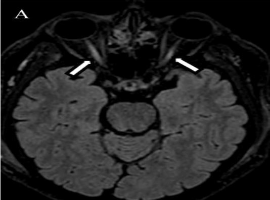

Citation: L. Jay-Caillierez, B. Allaouchiche, F. Cotton, et al. Acute Blindness After Lower Limb Injury. Clin Image Case Rep J. 2021; 3(3): 155.